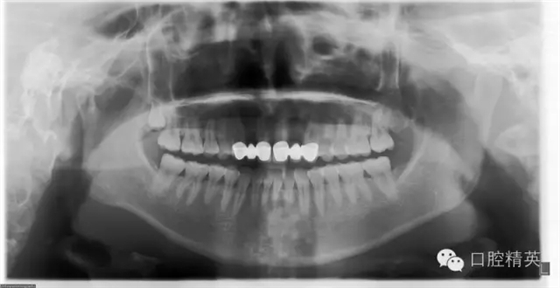

檢查:12及22缺失,13、12、11固定修復(fù)體,21、22、23固定修復(fù)體,11、13、21、23修復(fù)體邊緣不密合,修復(fù)體顏色偏黃,叩痛(—),不松動(dòng),13、23牙齦退縮,11、13、21、23牙齦發(fā)暗,覆牙合覆蓋關(guān)系大致正常。口腔衛(wèi)生狀況尚可。X線片示13、11、21及23牙根長度可,根尖區(qū)無明顯病變,牙槽骨無明顯吸收。12、22缺失。